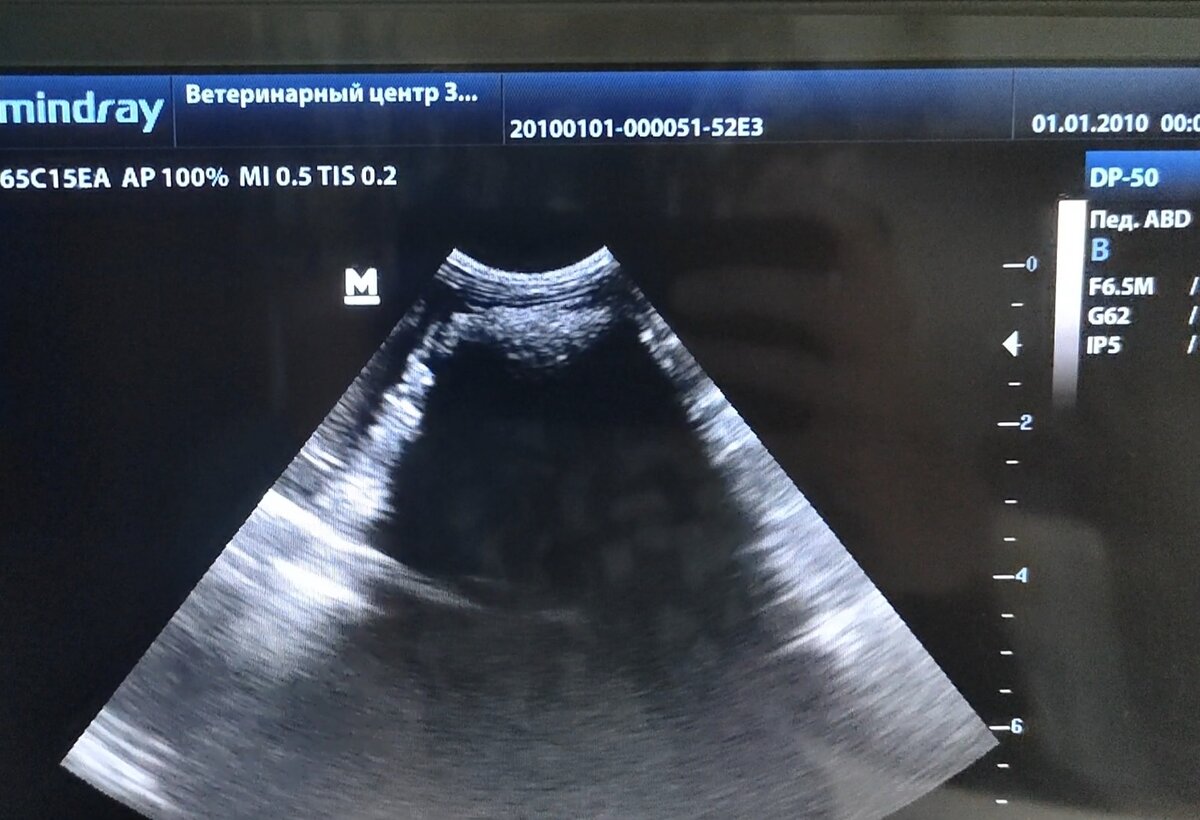

Во время проведения ультразвукового исследования было обнаружено округлое инородное тело с ровными, четкими границами, средней эхогенности, однородной эхоструктуры с артефактом дистального затемнения, размером 2,6 см на 1,52 см.